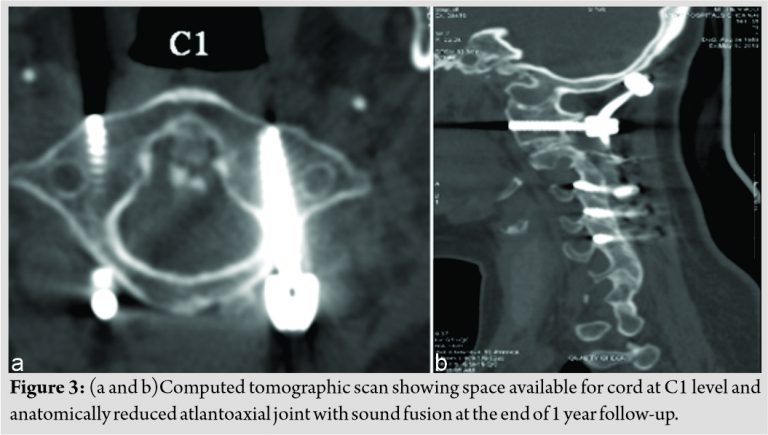

The patient was then positioned prone using the Mayfield’s clamp. The adequate reduction was ensured under fluoroscopic guidance. The standard posterior approach was performed to expose the atlantoaxial and occipitocervical region. C1-C2 joint was curetted, wedge-shaped bone graft was placed and fusion performed along with posterior fusion from occiput to C5 using occipital plate and lateral mass screws at C1, C3, C4, and C5. C1-C2 joint was reduced using DCER (distraction, compression, extension, and reduction) technique; hence, decompression was deferred as joint was reduced anatomically [8]. Sublaminar wires were used at the C2 lamina. The construct was stabilized with pre-bent rods. Posterior fusion was performed using cancellous graft chips obtained from the right posterior iliac crest (Fig. 2c). The post-operative period was uneventful, and the patient was advised to use the soft cervical collar for 3 months. By the end of 3 months, she recovered significantly from her myelopathic symptoms. CT scan performed at the end of 1 year demonstrated a well-reduced atlantoaxial joint adequate space available for cordand a maintained cervical sagittal alignment with sound fusion at C1-C2 joint (Fig. 3a and b).